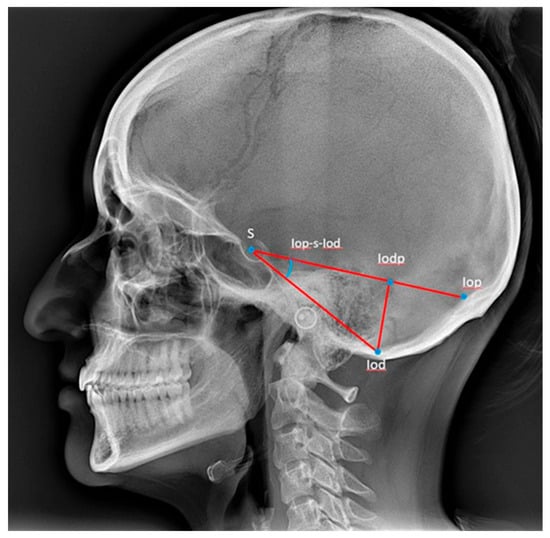

The measurement of the posterior cranial fossa dimensions was carried out according to Caspersen et al. [28], and reference points and lines are described in Table 2 and illustrated in Figure 3 [28].

Figure 3.

Reference points and lines used for the description of the posterior cranial fossa [28]. S: sella, the centre of the sella turcica. Iop: the internal occipital protuberance. Iod: the deepest point in the posterior cranial fossa. Iodp-Iop: the length from the internal occipital protuberance to the point Iodp. Iodp-Iod: the length from the point Iodp to the deepest point in the posterior cranial fossa. Iop-s-Iod: the angle between the Iop-S and the S-Iod lines. S-Iod: the length from sella to the deepest point in the posterior cranial fossa. S-Iop: the length from sella to the internal occipital protuberance.